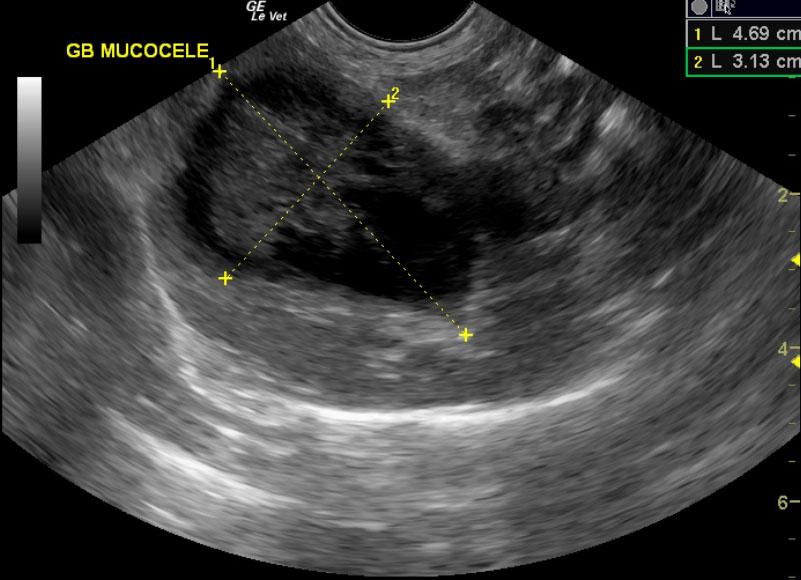

A 12-year-old FS Pomeranian was presented for acute vomiting and diarrhea. On physical examination, dyspnea, coughing, and a heart murmur were present. Urinalysis, T4, coagulation profile, and CBC were all within normal limits. Abnormalities on serum biochemistry were revealed elevated total proteins, globulin, liver enzyme activity, total bilirubin, and azotemia.